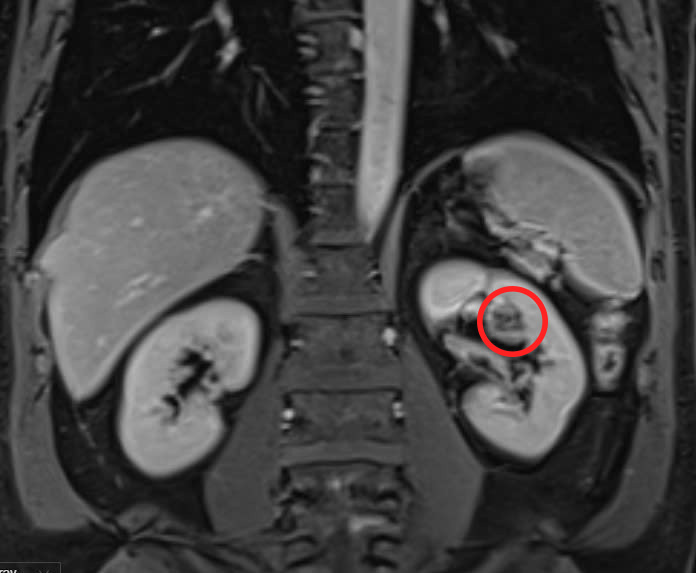

Dr. Nguyen Hoang Duc, Head of the Urology Department at the Urology - Nephrology - Andrology Center of Tam Anh General Hospital in Ho Chi Minh City, explained that Mr. Long's 12 mm tumor was located in the renal hilum, a critical area where arteries and veins enter and exit the kidney. This area also houses vital structures like the renal pelvis and ureter. Due to the high risk of bleeding, a biopsy was not possible. CT and MRI scans were conducted, suggesting renal cell carcinoma.

The cancerous kidney tumor located within the renal hilum, where major blood vessels pass. Photo: *Tam Anh General Hospital*

The tumor posed a risk of spreading to lymph nodes in the renal hilum or surrounding lymphatic system, and even early metastasis through the bloodstream. Traditional surgery carried a high risk of requiring a full nephrectomy due to the difficulty in controlling bleeding during the procedure.